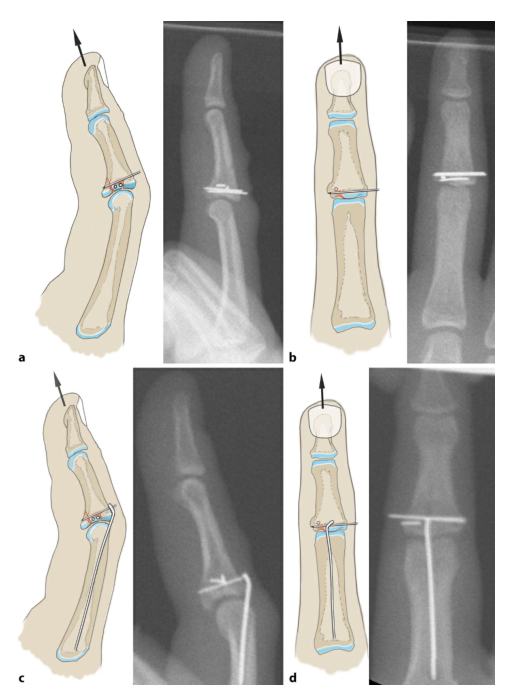

В случаях ортопедических переломов относительно распространены переломы основания средней фаланги, и Хинтрингер разделил эти переломы на четыре типа.

ТИП 1 Односторонний компрессионный перелом суставной поверхности с неповрежденными связками с обеих сторон (зеленый).

ТИП 2 Связка (красная) остается прикрепленной к ладонной костной массе, вызывая нестабильность сустава и подвывих.

ТИП 3 Опорная суставная поверхность на ладонной стороне разрушена и вся суставная поверхность сдавлена. Отделение костных фрагментов, прикрепленных к связкам (красный).

ТИП 4 Перелом распространяется в продольную ось, центральная зона сжатия расширена, наблюдается подвывих и осевое отклонение проксимального межфалангового сустава.